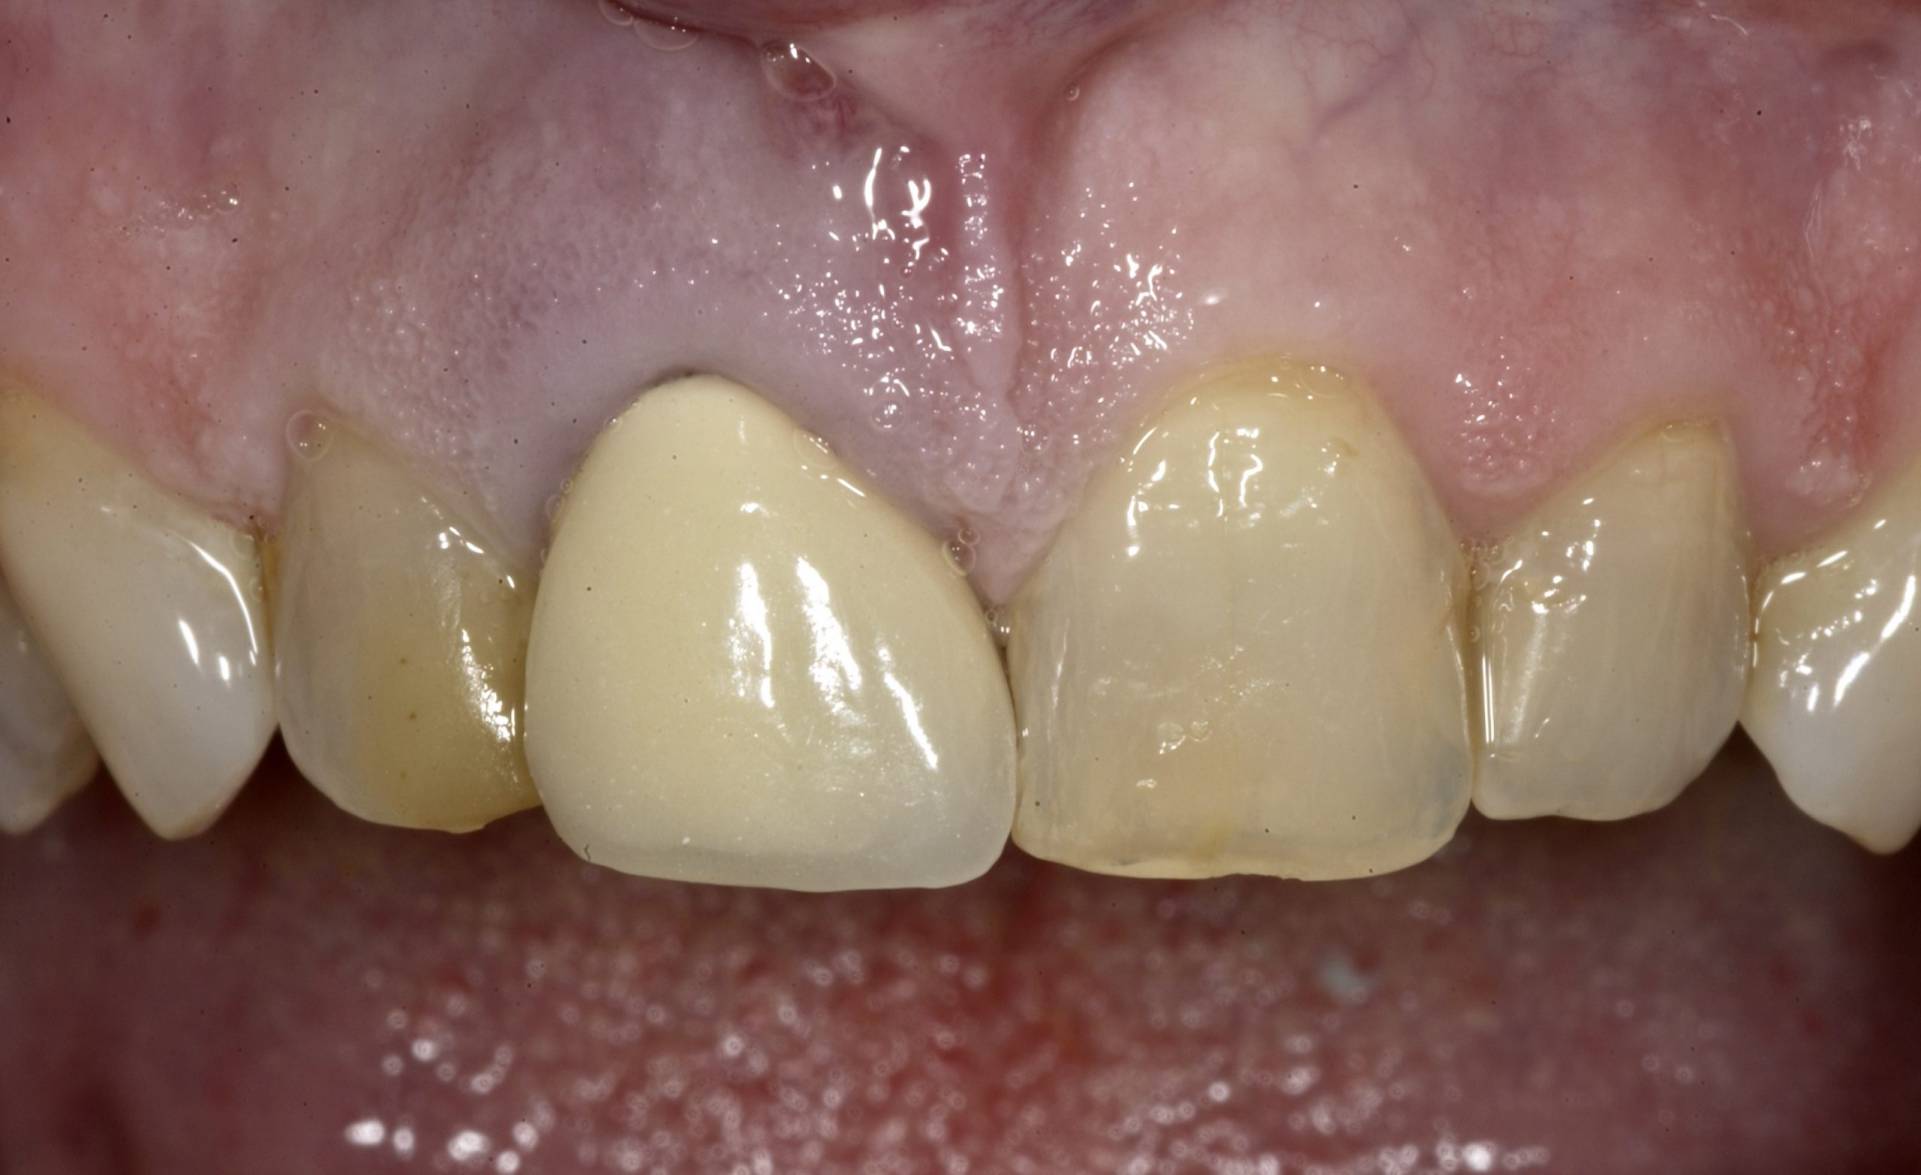

Mithilfe moderner Diagnostik, mikrochirurgischer Techniken und gewebeschonender Verfahren schaffen wir optimale Voraussetzungen für eine sichere Einheilung. Bei Bedarf werden knochenaufbauende Maßnahmen und biologische Regenerationskonzepte integriert, um auch in anspruchsvollen Situationen stabile Ergebnisse zu erzielen.

Das Ziel ist eine funktionell und ästhetisch perfekte Versorgung, die sich harmonisch in das bestehende Gebiss einfügt – für langfristige Stabilität, Sicherheit und ein natürliches Gefühl beim Kauen und Sprechen.